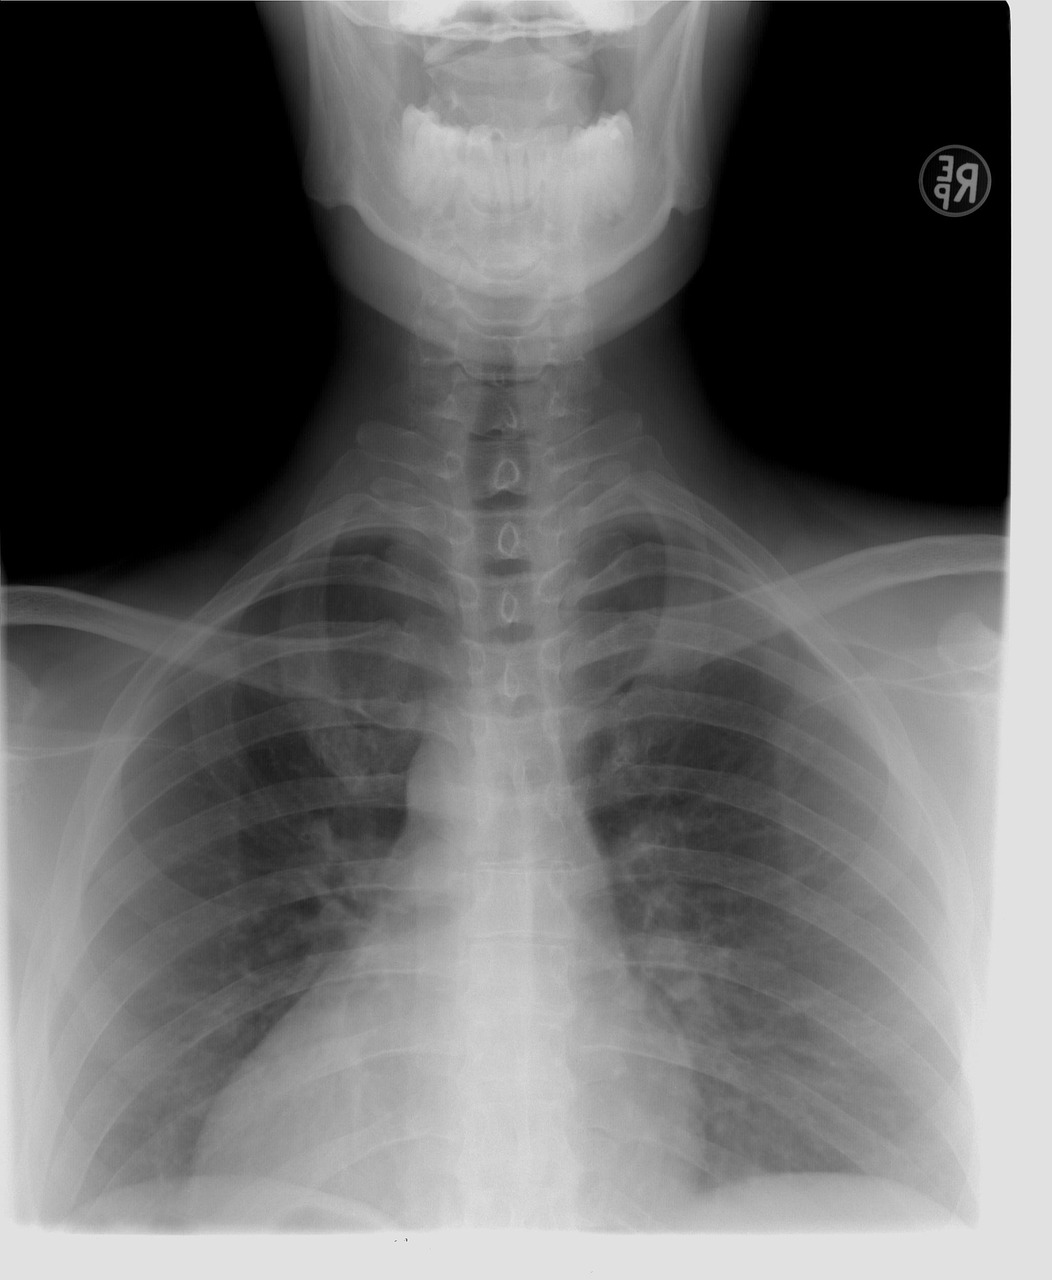

폐렴구균은 호흡기를 통해 전염되는 세균으로, 폐렴뿐 아니라 중이염, 부비동염, 패혈증, 뇌수막염 등 다양한 감염증의 원인이 된다. 그중에서도 폐렴은 고령층에게 가장 흔하게 발생하는 질환이며, 이는 입원과 사망으로 이어질 수 있어 결코 가볍게 볼 수 없다.

특히 65세 이상 노인, 심장병, 폐질환, 당뇨병 등 만성질환을 가진 사람, 흡연자, 면역저하자 등은 폐렴구균 감염에 취약하다. 국내 통계에 따르면 침습성 폐렴구균 감염증(IPD)의 치명률은 일반 폐렴보다 훨씬 높은 편이며, 고령자의 경우 감염 후 회복력이 떨어져 장기적인 후유증을 남길 수 있다.